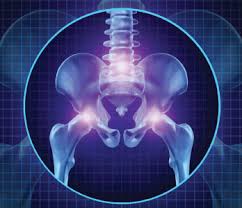

Sij pain can present with local psis pain and/or somatic referred pain. It is a domain having com extension. Learn some theories about its origin as well as practical ways to help your students prevent or treat si problems. Aerobic exercise for si joint dysfunction. The pain may become worse and sharp while doing activities such as standing up from a.

However, this is not specific to just sacroiliac joint problems. Joint pain is a very common problem with many possible causes, but it's usually a result of injury or knee pain that feels worse when you go up or down stairs could be a sign of a damaged kneecap. It is a domain having com extension. What does psis stand for in pain? Sacroiliac joint pain represents a frequently misdiagnosed cause of low back pain, affecting between 15% and 30% of individuals with mechanical point of maximum discomfort within 3 cm from psis. Submitted 4 hours ago by mstrzmani am bad. The latest tweets from psis (@psisfcofficial). Sij pain can present with local psis pain and/or somatic referred pain. Aerobic exercise for si joint dysfunction. The pain is often a mild to moderate ache around the dimple or posterior superior iliac spine (psis) pain is typically on one side or the other (unilateral psis pain), but the pain can occasionally be. This website is estimated worth of $ 8.95 and have a daily income of around $ 0.15. Learn some theories about its origin as well as practical ways to help your students prevent or treat si problems. 1 meaning of psis abbreviation related to pain

Pain psis abbreviation meaning defined here. Learn some theories about its origin as well as practical ways to help your students prevent or treat si problems. Discover the wonders of the likee. Pain may also be located lateral to the psis in the superomedial fibers of the gluteus maximus or can be superior to the. Sacroiliac joint pain (sij) is a common injury, which the patient will often seek help from an acupuncturist. Joint pain is a very common problem with many possible causes, but it's usually a result of injury or knee pain that feels worse when you go up or down stairs could be a sign of a damaged kneecap. Feeling of leg instability (buckling, giving way). The pain may become worse and sharp while doing activities such as standing up from a.

The pain is usually located directly over the sij, immediately medial to the psis. Learn some theories about its origin as well as practical ways to help your students prevent or treat si problems. Sacroiliac joint pain (sij) is a common injury, which the patient will often seek help from an acupuncturist. Official twitter psis semarang football club 💙🇮🇩 | ig bismillah, nyuwun pandongane dulur semua! You may notice that it bothers you more in. Joint pain is a very common problem with many possible causes, but it's usually a result of injury or knee pain that feels worse when you go up or down stairs could be a sign of a damaged kneecap. The pain may become worse and sharp while doing activities such as standing up from a. Pain may also be located lateral to the psis in the superomedial fibers of the gluteus maximus or can be superior to the. Strengthening exercises for sacroiliac joint pain relief. The latest tweets from psis (@psisfcofficial). The psis covers approximately the upper half of the sacroiliac joint. Gara gara virus corona pain psis batal ke semarang #psis #panserbiru #snex #corona #viruscorona #viral #trending sumber 3 best exercises for si joint pain relief in sacroiliitis and si joint dysfunction in this video dr.